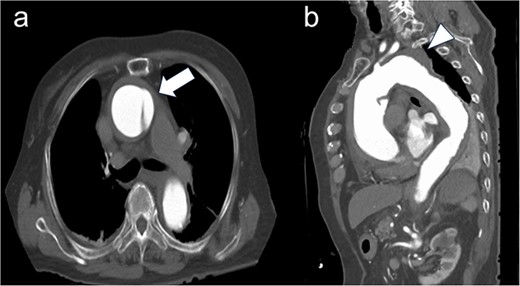

After primary aortography was performed using a 5-F pigtail catheter, the landing zones were marked; the introducer was inserted; and the endoprosthesis was tracked and centred over the aneurysm under fluoroscopic guidance, deployed and subsequently ballooned in Zone 2. Angiography revealed a type 1 endoleak; therefore, inflation with a trilobe balloon was performed. Two 8 × 20 cm coils (Interlock™, Boston Scientific, Marlborough, Massachusetts) were introduced through the left subclavian artery into the aneurysms for embolization. The final angiogram showed a slight leak in the aneurysm; however, the blood flow was determined to be from the left subclavian artery, and the procedure was terminated. Although contrast-enhanced CT performed on postoperative Day 8 showed a type 4 endoleak (Fig. 2). The postoperative course was uneventful, and she was discharged on Day 15.

Postoperative enhanced-computed tomography findings. There were no problematic findings, although a slight type 4 endoleak was present.